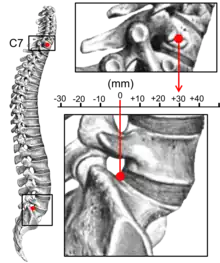

Kyphosis can be graded in severity by the Cobb angle. Also, sagittal balance can be measured. The sagittal balance is the horizontal distance between the center of C7 and the superior-posterior border of the endplate of S1 on a lateral radiograph.[15]